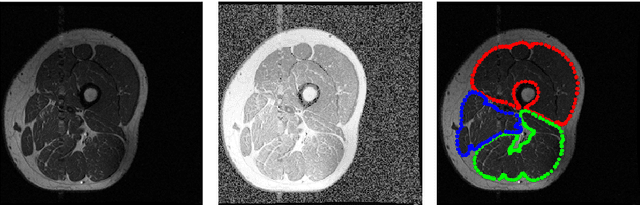

Image segmentation is a crucial but challenging task that has many applications. In medical imaging for instance, intensity inhomogeneity and noise are common. In thigh muscle images, different muscles are closed packed together and there are often no clear boundaries between them. Intensity based segmentation models cannot separate one muscle from another. To solve such problems, in this work we present a segmentation model with adaptive spatial priors from joint registration. This model combines segmentation and registration in a unified framework to leverage their positive mutual influence. The segmentation is based on a modified Gaussian mixture model (GMM), which integrates intensity inhomogeneity and spacial smoothness. The registration plays the role of providing a shape prior. We adopt a modified sum of squared difference (SSD) fidelity term and Tikhonov regularity term for registration, and also utilize Gaussian pyramid and parametric method for robustness. The connection between segmentation and registration is guaranteed by the cross entropy metric that aims to make the segmentation map (from segmentation) and deformed atlas (from registration) as similar as possible. This joint framework is implemented within a constraint optimization framework, which leads to an efficient algorithm. We evaluate our proposed model on synthetic and thigh muscle MR images. Numerical results show the improvement as compared to segmentation and registration performed separately and other joint models.